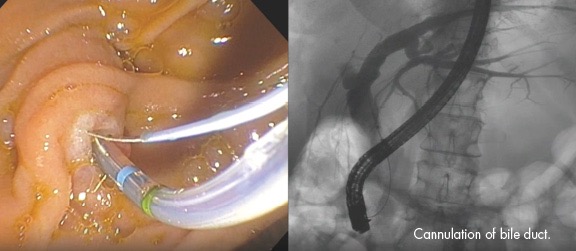

4) post-ERCP pancreatitis: 내시경적 역행성 담췌관조영술(ERCP) 이후 발생

1) 내시경적 역행성 담췌관조영술(ERCP)

- 담석 혹은 담도염의 증거가 있는 경우에 시행한다. 뚜렷한 증거 없이 진단적 목적으로 시행하지 않는다.